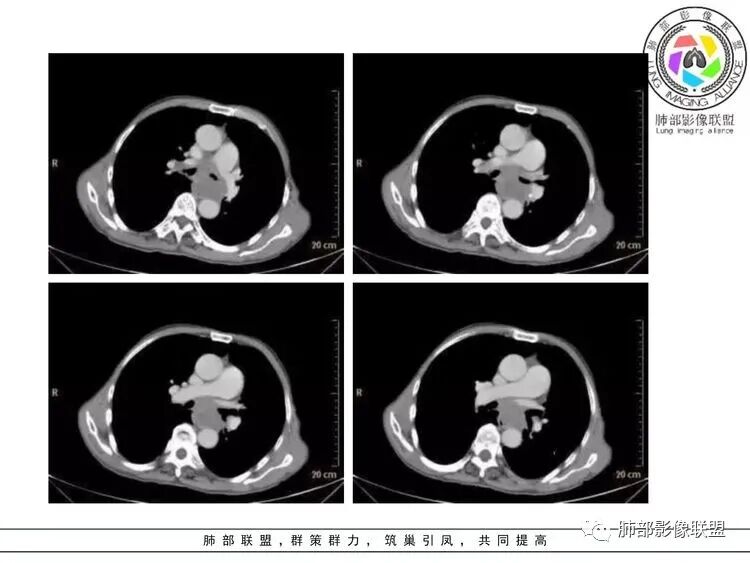

老年男性,右侧肺门可见团块状占位包绕气管,气管受压变窄,纵隔见巨大团块状占位,另纵隔可见肿大淋巴结,增强肺门及纵隔肿块强化不明显,内部可见血管影,周围结构只是受压移位,另颌下淋巴结穿刺慢性淋巴结炎,首先考虑小细胞癌,鉴别淋巴瘤、结节病。

右肺下叶小结节,右肺门及中后纵膈淋巴结肿大融合,强化均匀,主支气管、中间段及下叶支气管受压变窄,右下肺静脉受压变窄,考虑小细胞癌,鉴别淋巴瘤

老年男性,纵隔及肺门多发肿大淋巴结,相互融合呈团块状,包绕支气管官腔,呈针尖样狭窄,增强后轻度强化,考虑小细胞肺癌

纵隔及肺门淋巴结肿大相互融合呈冰冻纵膈,支气管受压变窄呈针孔样,老年男性吸烟患者,考虑小细胞肺癌。

老年男性,有吸烟史,双颈部肿块,双肺纵隔淋巴结多发淋巴结肿大并融合成块,气管及右肺下叶支气管受压狭窄,考虑恶性,淋巴瘤可能,鉴别小细胞肺癌。

老年男性,有吸烟史,右肺下叶背段示小结节,纵隔、腋窝及右肺门淋巴结节肿大,气管受压狭窄,后纵隔软组织内示血管走行,考虑小细胞>淋巴瘤。

晨读老年男性,长期吸烟。右肺门、纵隔多发肿大淋巴结、融合成团块,中间支气管、右肺下叶支气管受压变窄,增强扫描强化程度较轻,血管包埋。另两侧腋窝亦见多发肿大淋巴结。常规恶性没问题,小细胞?淋巴瘤?但是於老师的病例总感觉没那么简单。

纵隔内中后纵隔及右肺门淋巴结肿大,形成大肿块,整体密度均匀,并轻度强化,见“血管飘浮”征,包绕气管分叉及右主支气管及中间段支气管明显受压狭窄,并包埋右肺门血管束,无侵蚀破坏,右肺动脉后壁见压迹影,右肺下叶背段有阻塞性炎症,首选淋巴瘤,支气管超声内镜活检,明确诊断!